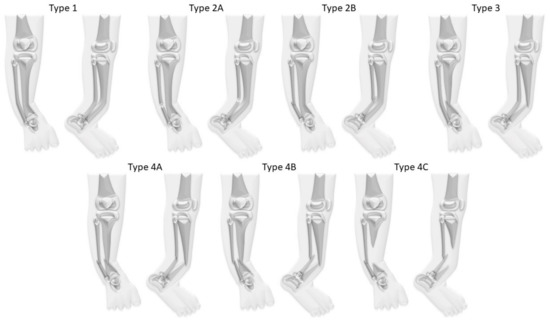

Congenital pseudarthrosis of the tibia (CPT) is a rare condition of unclear etiology [1]. The estimated prevalence of association with neurofibromatosis (NF) type 1 is 55%, even though van Royen et al. recently indicated that the true prevalence might be significantly higher (up to 84%) [2,3,4,5,6]. In most cases the pseudarthrosis is not yet present at birth, but the tibia shows a characteristic anterolateral bowing which deteriorates during growth (Figure 1). A fracture frequently develops spontaneously or after a minor trauma. This leads to a pseudarthrosis with atrophy of the bone ends and a surrounding soft tissue hamartoma impeding physiological healing [7,8,9]. The loss of remodeling potential and the growth inhibition of the tibia lead to further deterioration of the deformity and to leg length discrepancy (LLD) [7].

Figure 1. Clinical and radiological presentation of anterolateral bowing in congenital pseudarthrosis of the tibia (CPT); (A,B) anterior-posterior (a.p.) view; (C,D) lateral view.